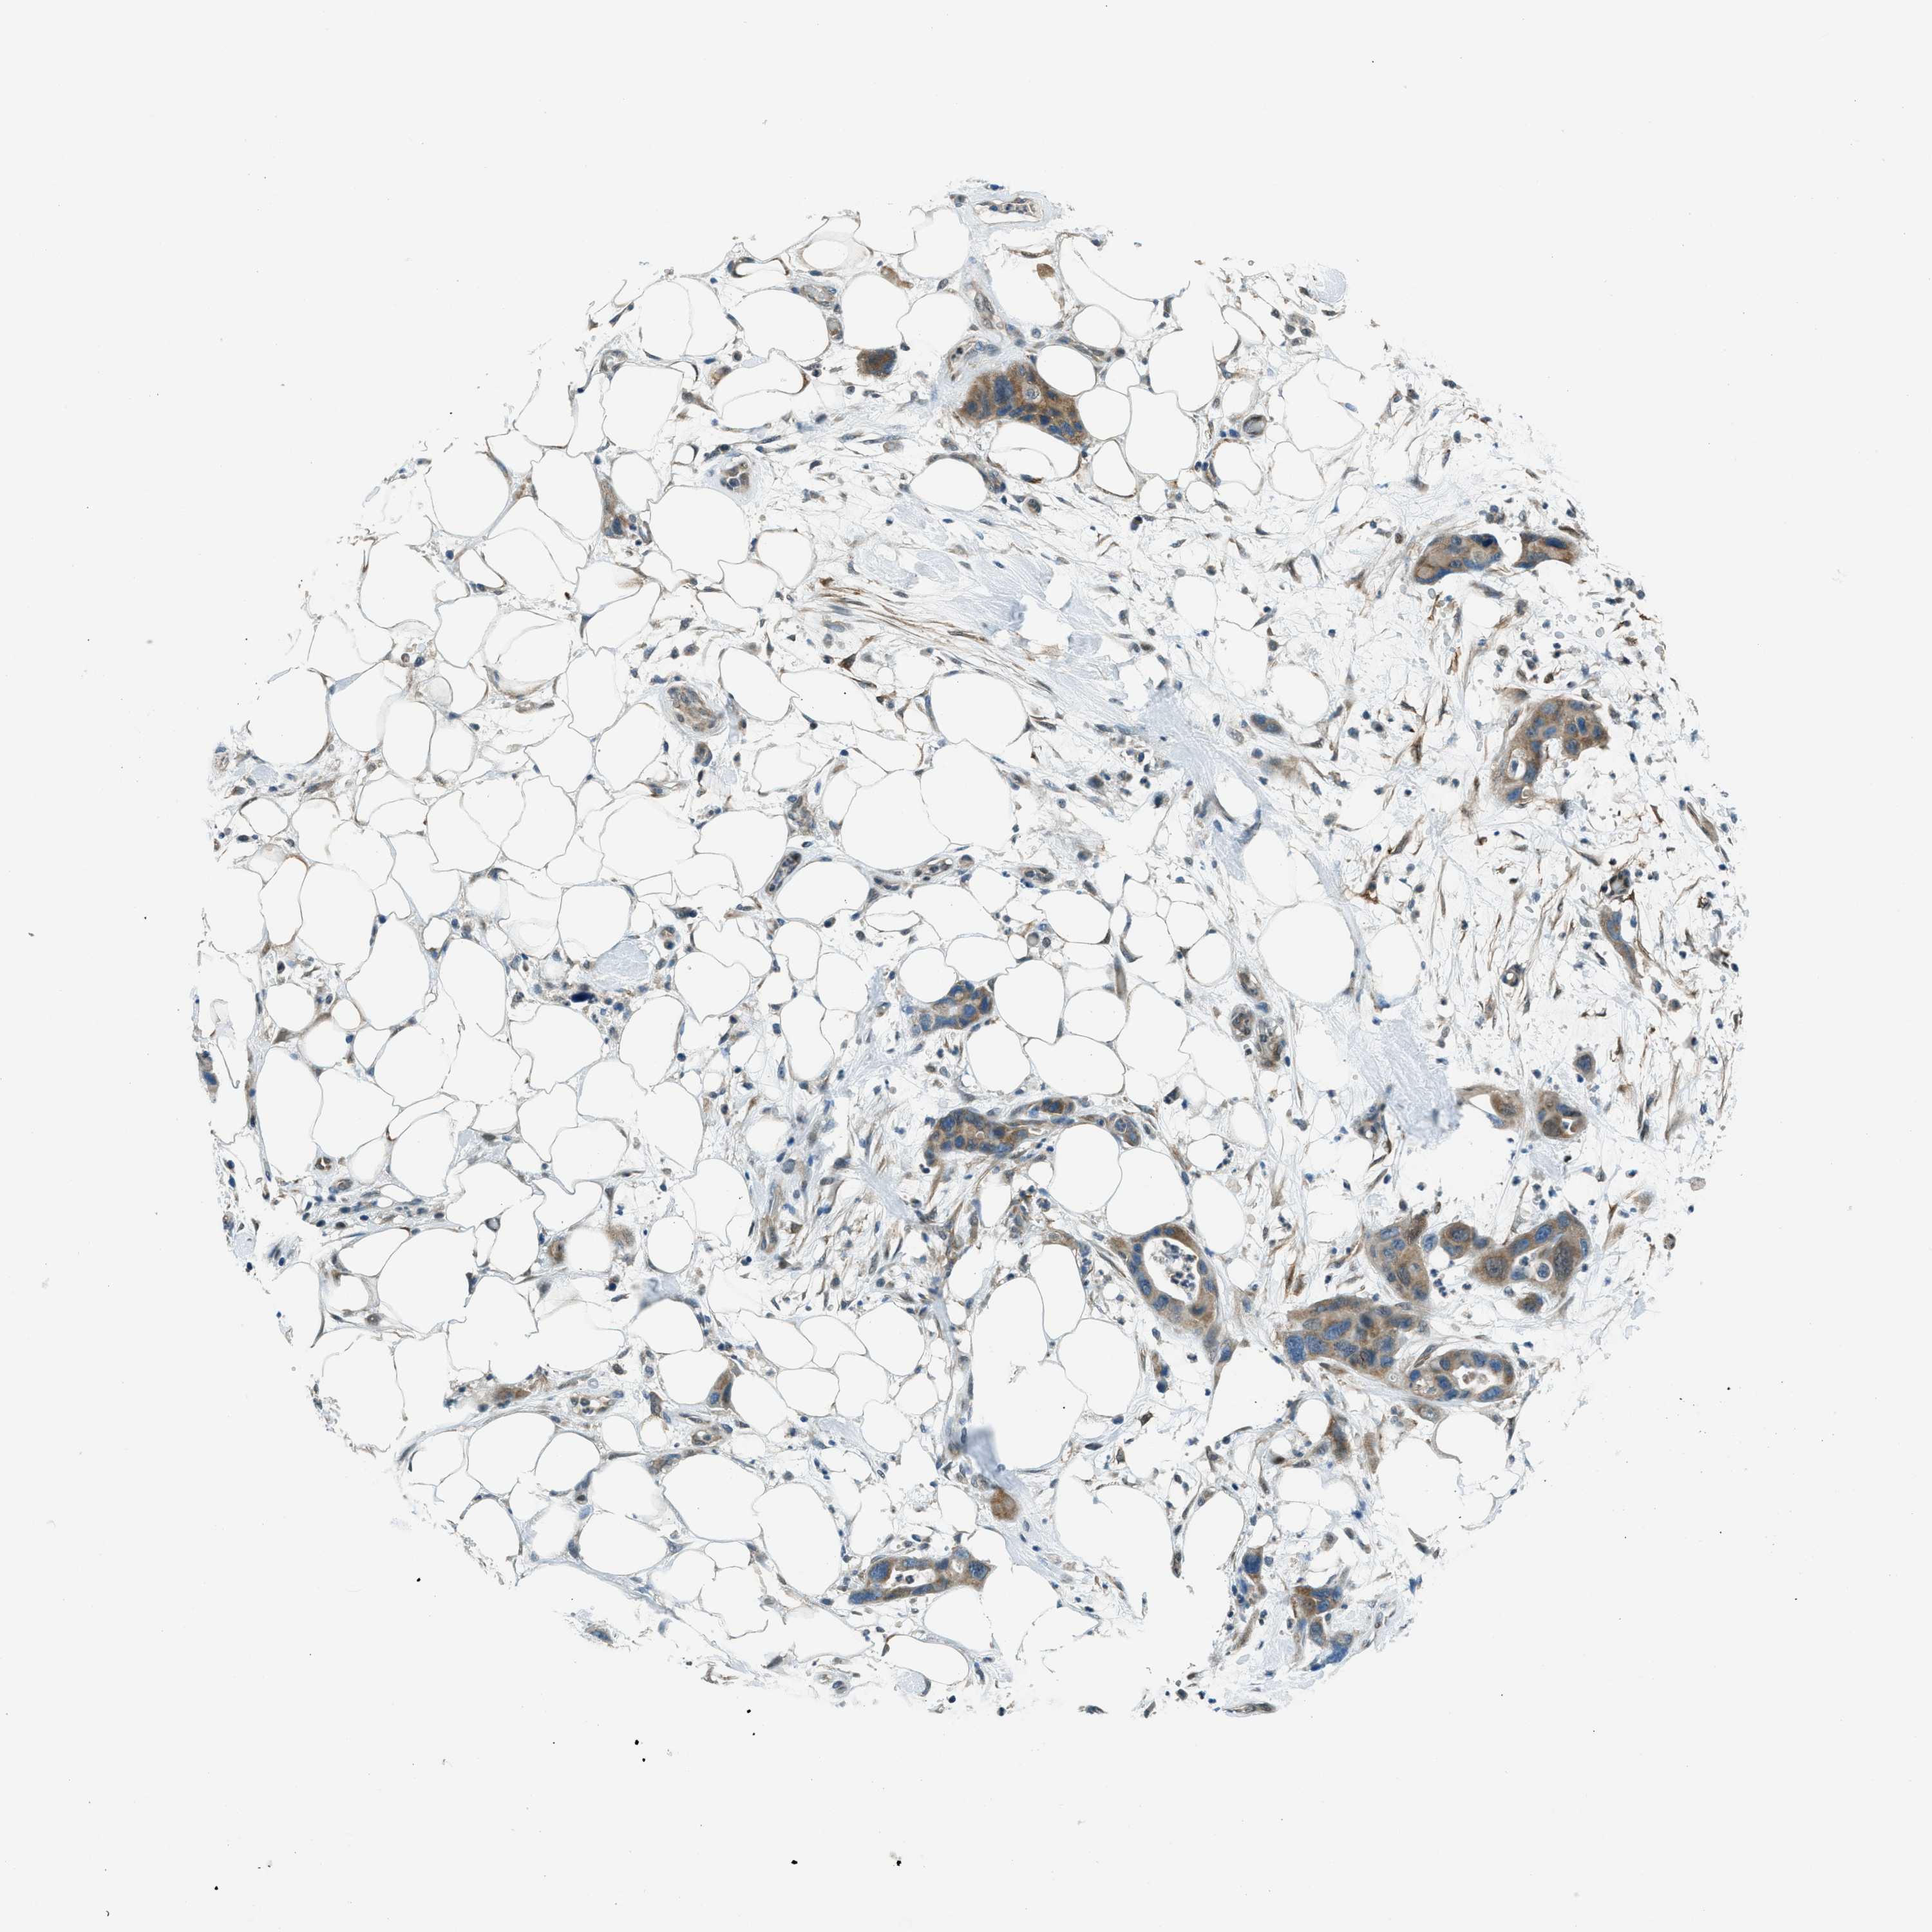

PANCREATIC CANCER - Protein expressioni

A mouse-over function shows sample information and annotation data. Click on an image to view it in a full screen mode. Samples can be filtered based on level of antibody staining by selecting one or several of the following categories: high, medium, low and not detected. The assay and annotation is described here.

Note that samples used for immunohistochemistry by the Human Protein Atlas do not correspond to samples in the TCGA dataset.

Antibody stainingi

Antibody staining in the annotated cell types in the current human tissue is reported as not detected, low, medium, or high, based on conventional immunohistochemistry profiling in selected tissues. This score is based on the combination of the staining intensity and fraction of stained cells.

Each image is clickable and will lead to virtual microscopy that enables deeper exploration of all samples and also displays staining intensity scores, fraction scores and subcellular localization as well as patient and tissue information for each sample.

Antibody HPA036356

Antibody CAB004986

Antibody CAB017025

Staining

High

Medium

Low

Not detected

Intensity

Strong

Moderate

Weak

Negative

Quantity

>75%

75%-25%

<25%

None

Location

Nuclear

Cytoplasmic/membranous

Cytoplasmic/membranous,nuclear

Adenocarcinoma, NOS

Adenocarcinoma, metastatic, NOS